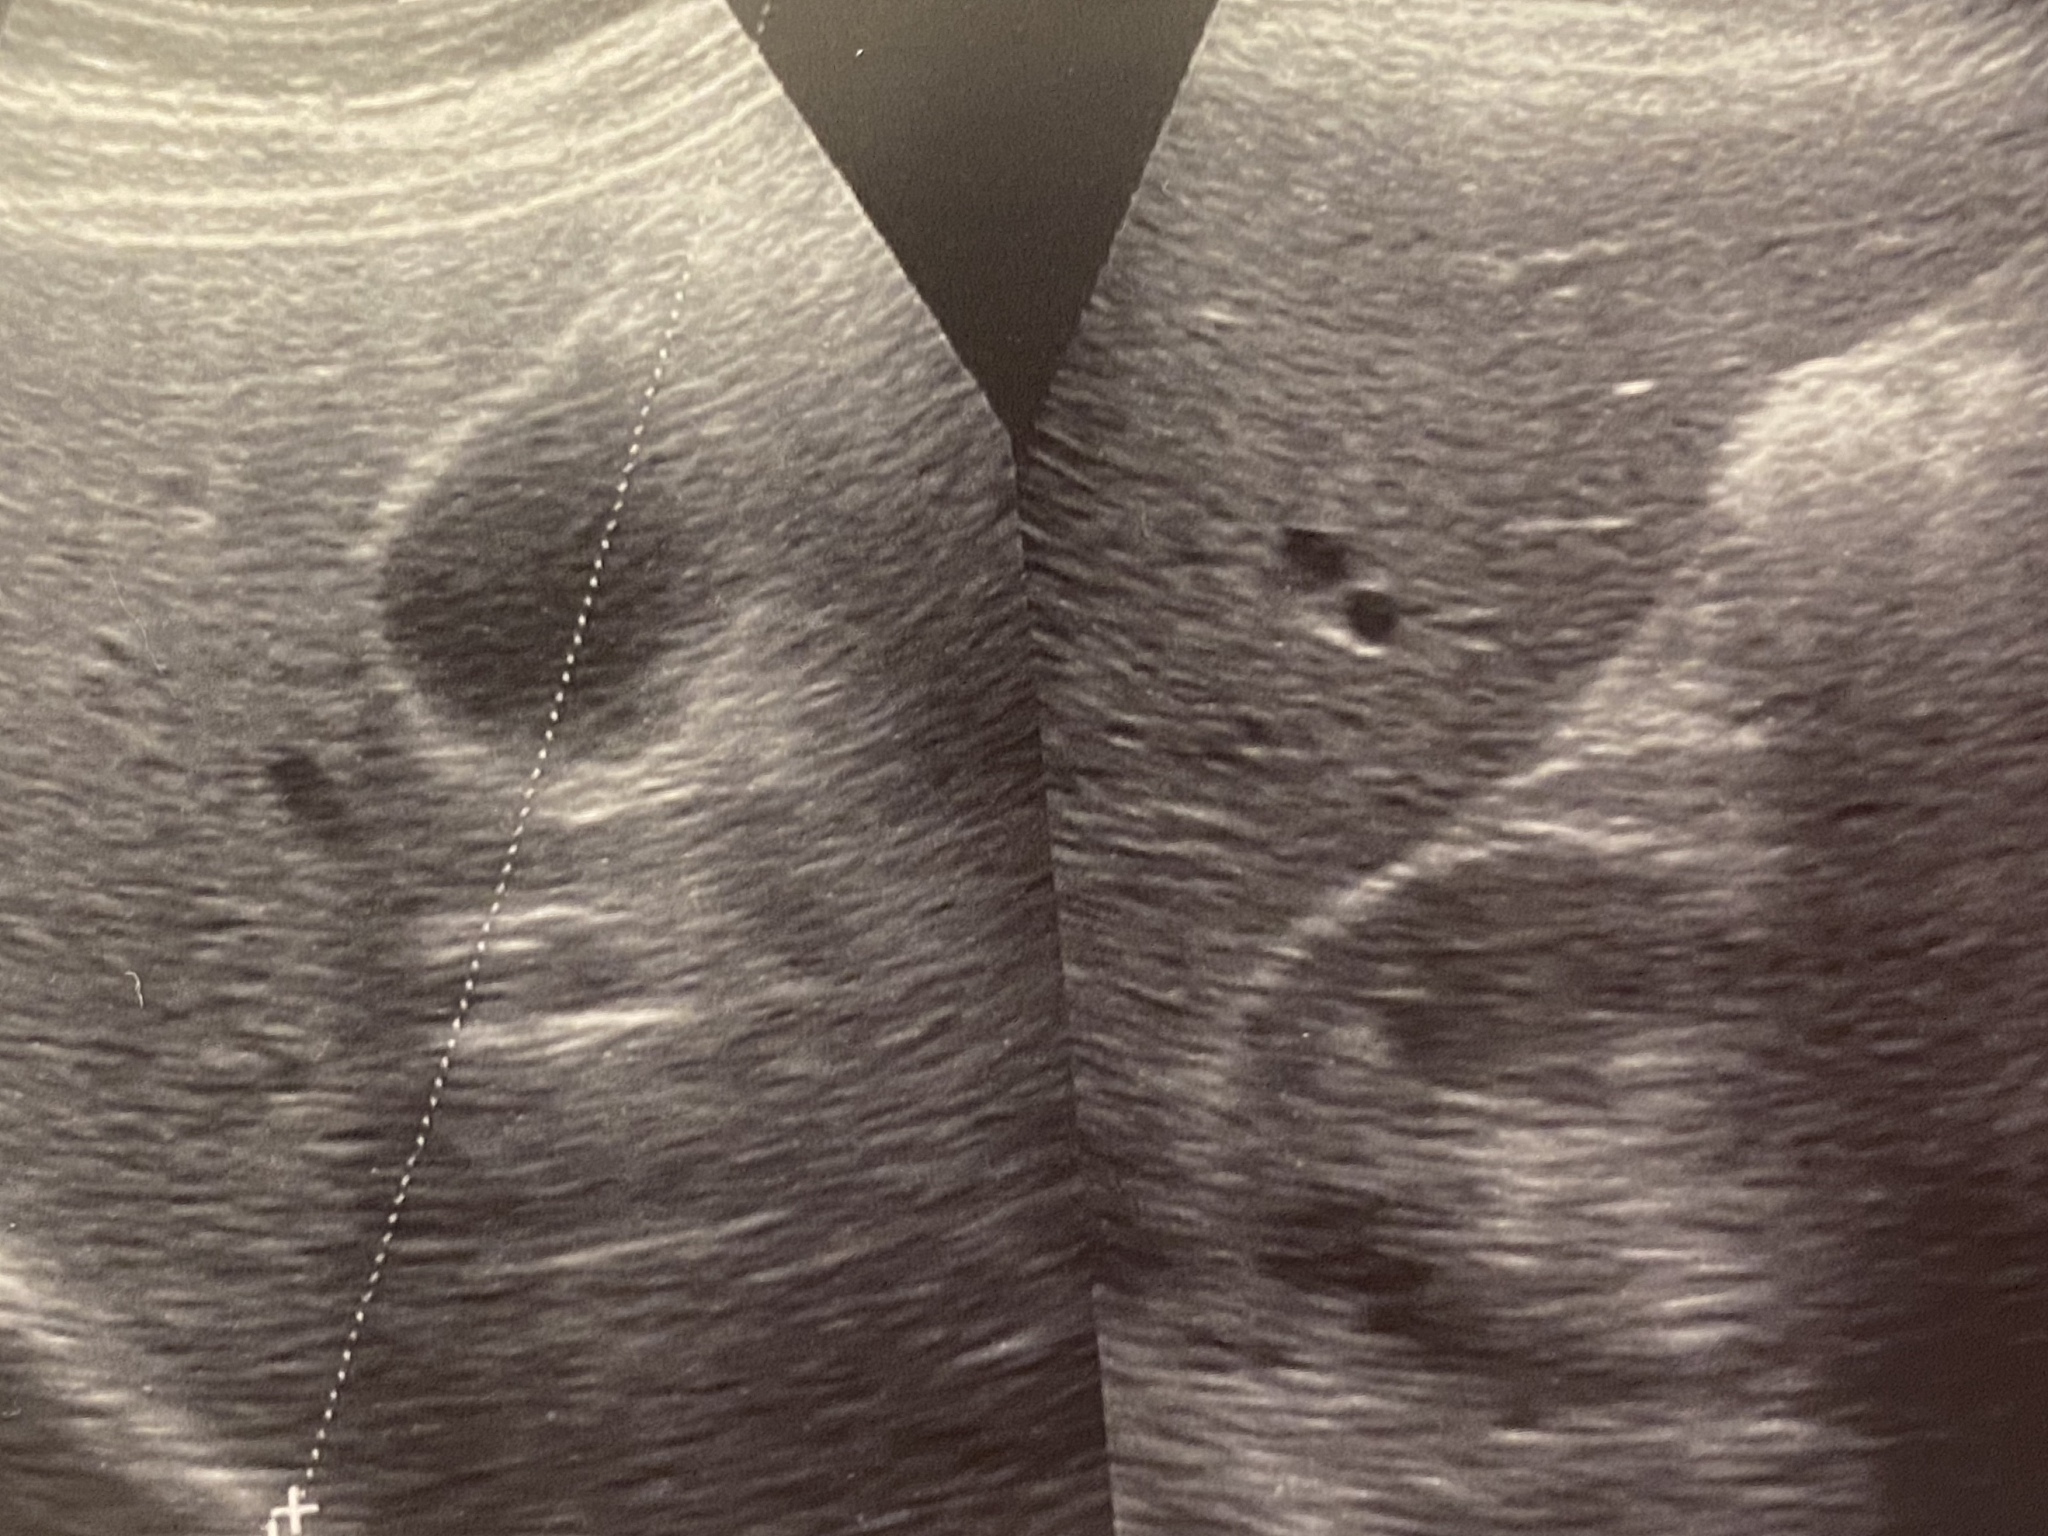

为了更明确地诊断,在获得患者知情同意后,进行了超声造影检查。'Further to clarify the diagnosis, an ultrasound contrast examination was performed with the patient's informed consent.'